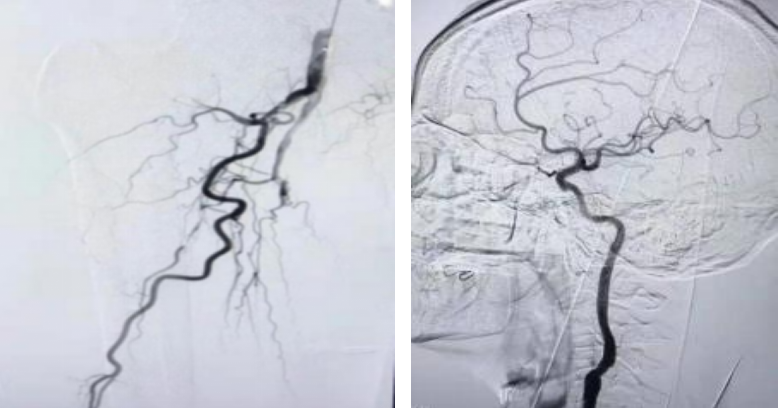

二、外周血管疾病: 常规开展外周动脉狭窄闭塞、动静脉瘘、动静脉血栓形成、血管畸形和静脉曲张、静脉溃疡、糖尿病足、布加综合征等疾病的综合治疗。

3. 多样化的外周血管疾病治疗:目前面临多种类型的外周血管病变,如:颈动脉体瘤、颈内动脉狭窄、下肢动脉硬化闭塞症、肺栓塞、下肢深静脉血栓、肠系膜上动脉夹层等疾病,我科能根据患者病情制定个体化治疗方案,采取介入手术与开放手术相结合的治疗模式,为患者选择最优治疗方案,提高疾病治愈率,降低并发症发生率,明显改善患者预后